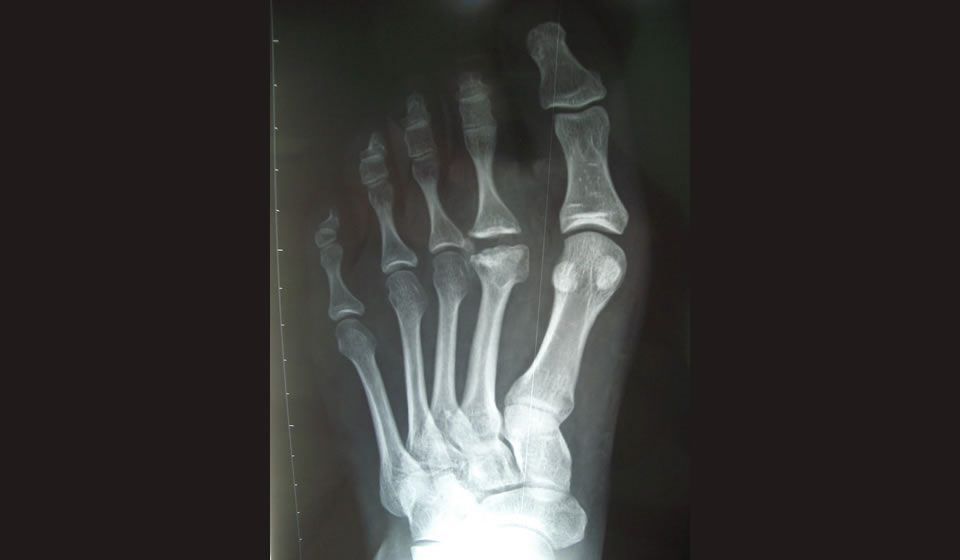

La radiografía es el que confirma el diagnóstico. Los hallazgos iniciales son: ensanchamiento del espacio intraarticular por 3 a 6 semanas luego del comienzo de la sintomatología. Esto es seguido por un aumento de la densidad del hueso subcondral. Al progresar la enfermedad una zona de rarefacción se desarrolla rodeado por un halo esclerótico. Con el tiempo el hueso epifisario se debilita y colapsa con la formación de osteofitos y cuerpos libres.

Estadío 1: comienza con una fractura por stress, la epífisis se encuentra isquémica, se ve un aumento en la densidad ósea.

Estadío 2: existe una absorción del hueso con un hundimiento de la porción central del hueso dentro de la cabeza del metatarsiano.

Estadío 3: se ven proyecciones óseas a cada lado de la cabeza, el cartílago articular plantar permanece intacto.

Estadío 4: hay compromiso del cartílago articular plantar, pueden verse fracturas y cuerpos libres.

Estadío 5: hay achatamiento de la cabeza del metatarsiano y artrosis.